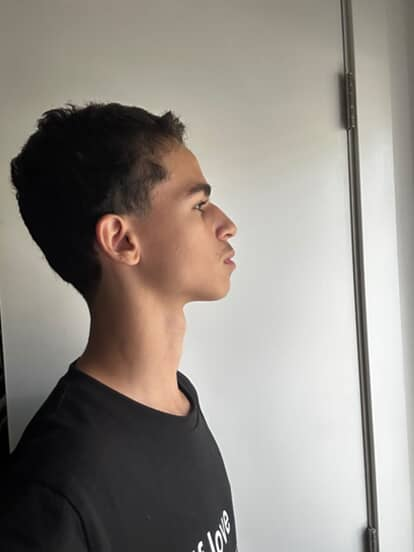

View attachment 4232105 Thoughts on the treatment plan my ortho gave me i just wanna fix my convex profile that i developed thru bad habits is their any diy thing i can do + any advice for my coloring etc

View attachment 4232105 Thoughts on the treatment plan my ortho gave me i just wanna fix my convex profile that i developed thru bad habits is their any diy thing i can do + any advice for my coloring etc

View attachment 4232105 Thoughts on the treatment plan my ortho gave me i just wanna fix my convex profile that i developed thru bad habits is their any diy thing i can do + any advice for my coloring etc

View attachment 4232105 Thoughts on the treatment plan my ortho gave me i just wanna fix my convex profile that i developed thru bad habits is their any diy thing i can do + any advice for my coloring etc

View attachment 4232105 Thoughts on the treatment plan my ortho gave me i just wanna fix my convex profile that i developed thru bad habits is their any diy thing i can do + any advice for my coloring etc

View attachment 4232105 Thoughts on the treatment plan my ortho gave me i just wanna fix my convex profile that i developed thru bad habits is their any diy thing i can do + any advice for my coloring etc